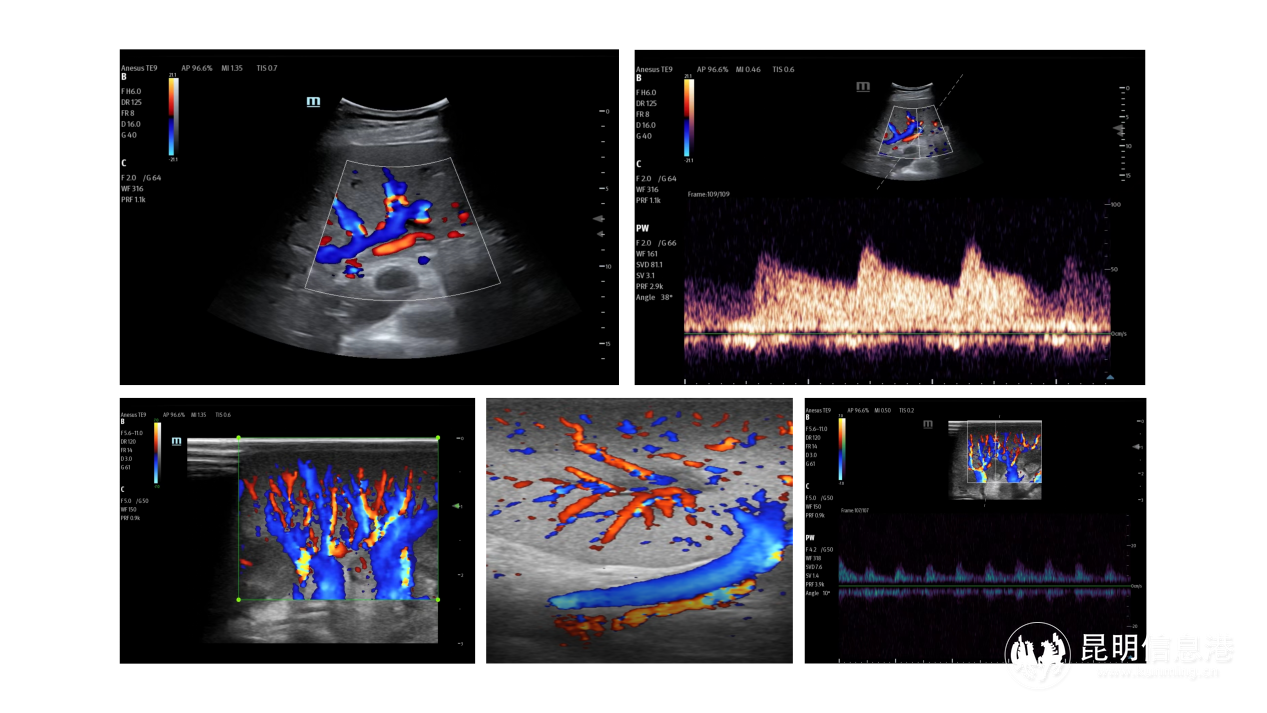

术后B超检查显示,移植肝脏、肾脏血流灌注良好

超声医学科曹维涵主任在术中术后动态监测移植器官血流状态